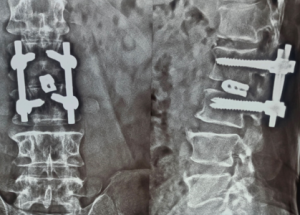

Expert spine services including minimally invasive surgery, pain management, and deformity correction.